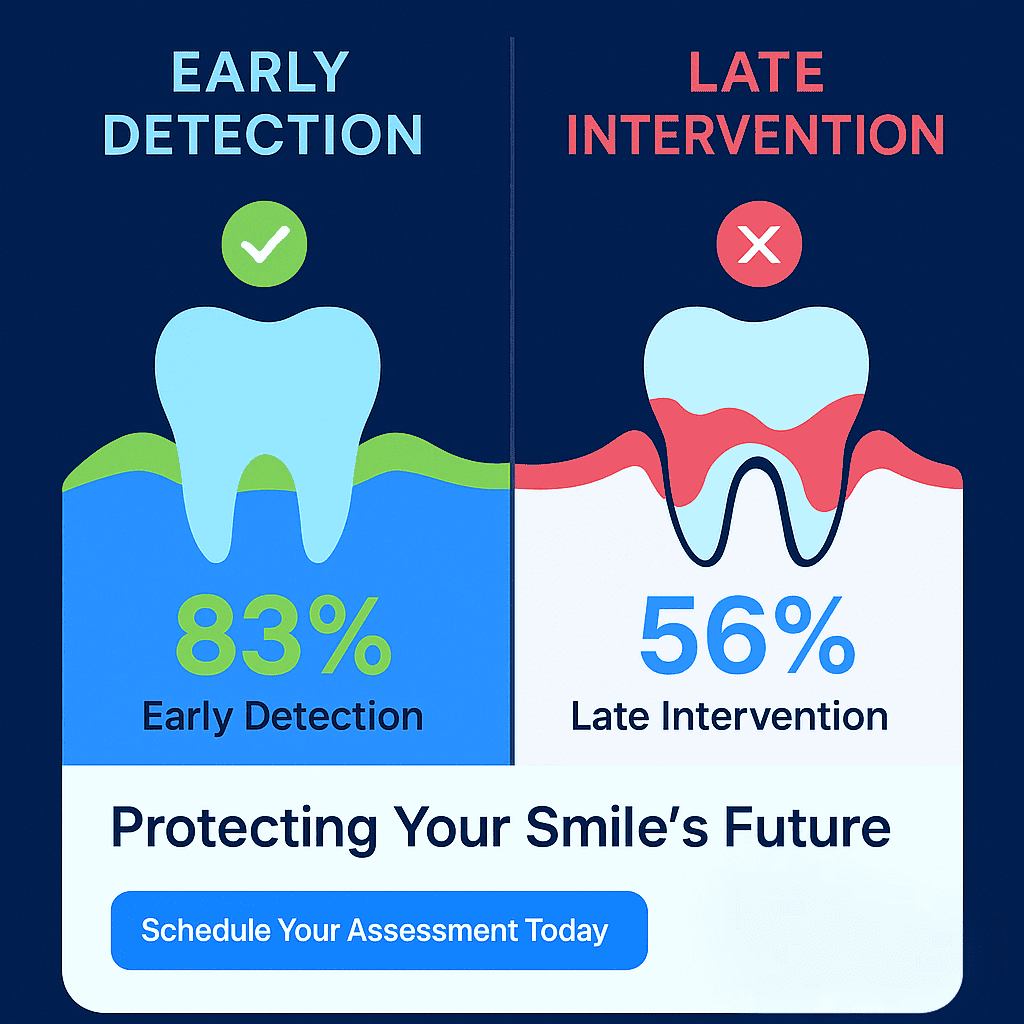

One of the most critical factors in implant success is timing. When a loose tooth is removed and immediately replaced with an implant, the bone loss can be minimized.

However, if you wait until the tooth falls out on its own or the bone has deteriorated significantly, additional procedures like bone grafting may be necessary before implant placement.

This is why many periodontists recommend being proactive rather than reactive when dealing with loose teeth. Early intervention often leads to simpler treatment and better long-term outcomes.